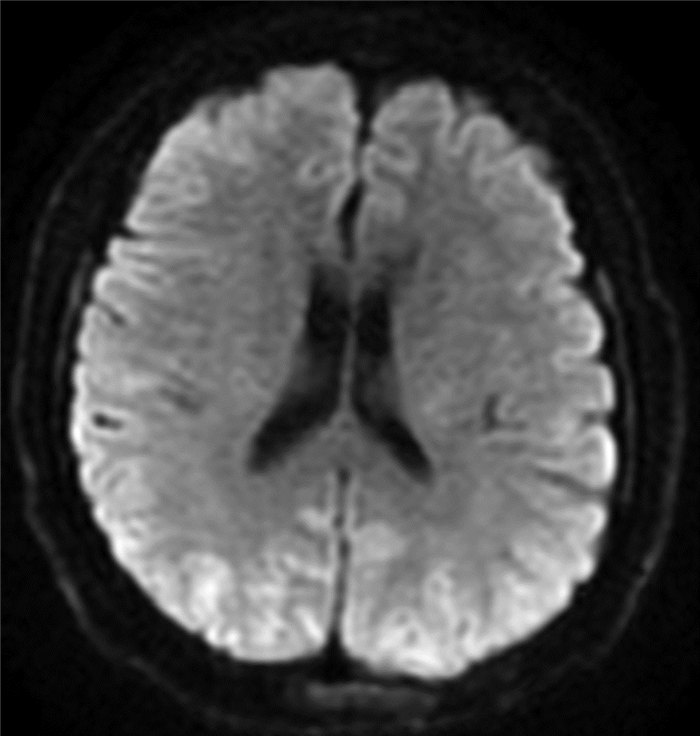

Endoscopic treatment of gastroesophageal varices complicated by posterior reversible encephalopathy syndrome: A case report

Tingting YU, Shanshan JIANG, Mengran ZHU, Yun BAI

2022, 38(1): 177-179. DOI: 10.3969/j.issn.1001-5256.2022.01.030

Abstract(830) HTML (198) PDF (3069KB)(60)

Abstract: